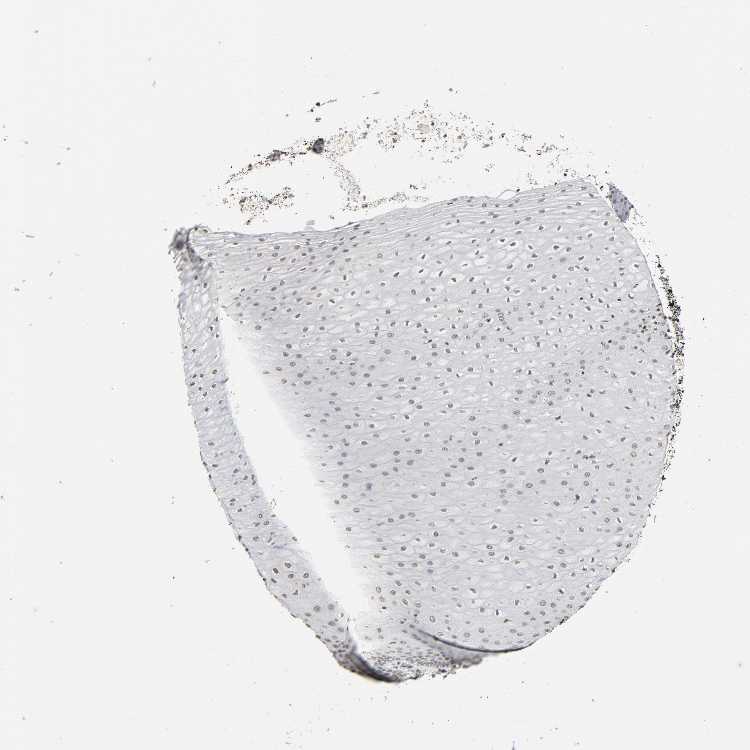

ESOPHAGUS - Antibody stainingi

Antibody staining in the annotated cell types in the current human tissue is reported as not detected, low, medium, or high, based on conventional immunohistochemistry profiling in selected tissues. This score is based on the combination of the staining intensity and fraction of stained cells.

Each image is clickable and will lead to virtual microscopy that enables deeper exploration of all samples and also displays staining intensity scores, fraction scores and subcellular localization as well as patient and tissue information for each sample.

Antibody HPA015270Antibody CAB004038

Squamous epithelial cells LowNot detected